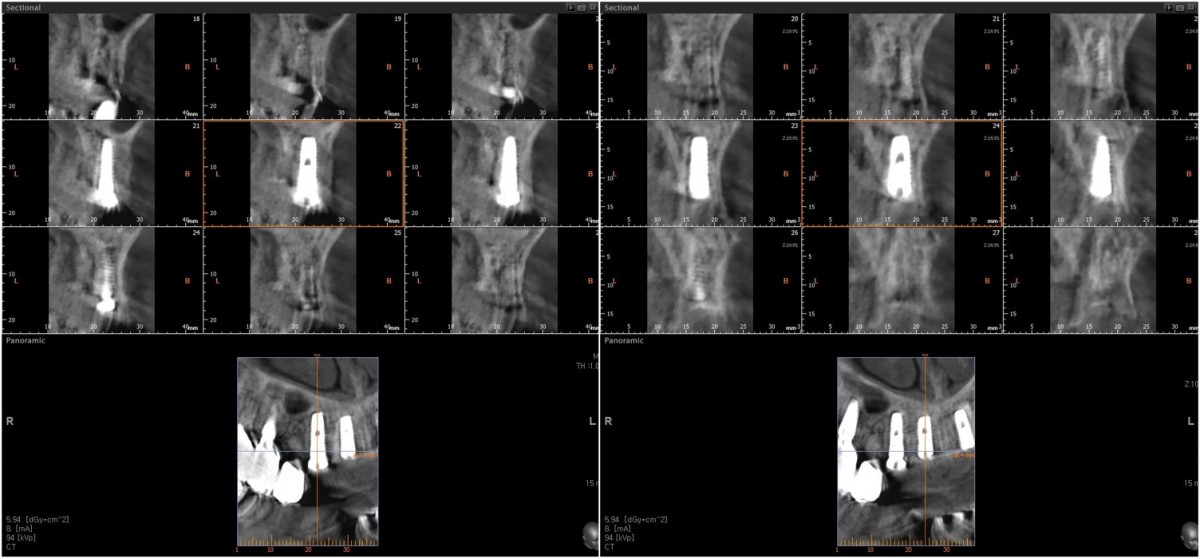

Anterior implant placement with Arum implant system in the maxilla.

A 46-year-old female patient didn’t

have any systemic problems but a poor oral condition.

The patient is scheduled

for the implant and general prosthetic restoration in various parts. First of

all, the vertical stop is completed by several prostheses in the posterior

region, and the final stage of intraoral restoration is to proceed with an

anterior implant installation.

▲Fixture to be placed. Arum® implant NB1